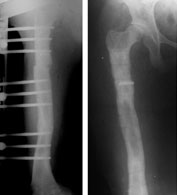

The final x-ray pictures just before fixator removal (left) and just after fixator removal (right).

The picture on the right is taken right after the fixator removal. The radiolucent shadow is the broken piece of threaded screw impacted in the bone. Also seen are the tracts left behind in the bone in the places where the schanz screws had been before removal. These tracts get filled up with new bone in about 3 weeks time. During this time we advise “careful weight bearing,” i.e. walk full weight-bearing with the aid of a crutch or a stick. |